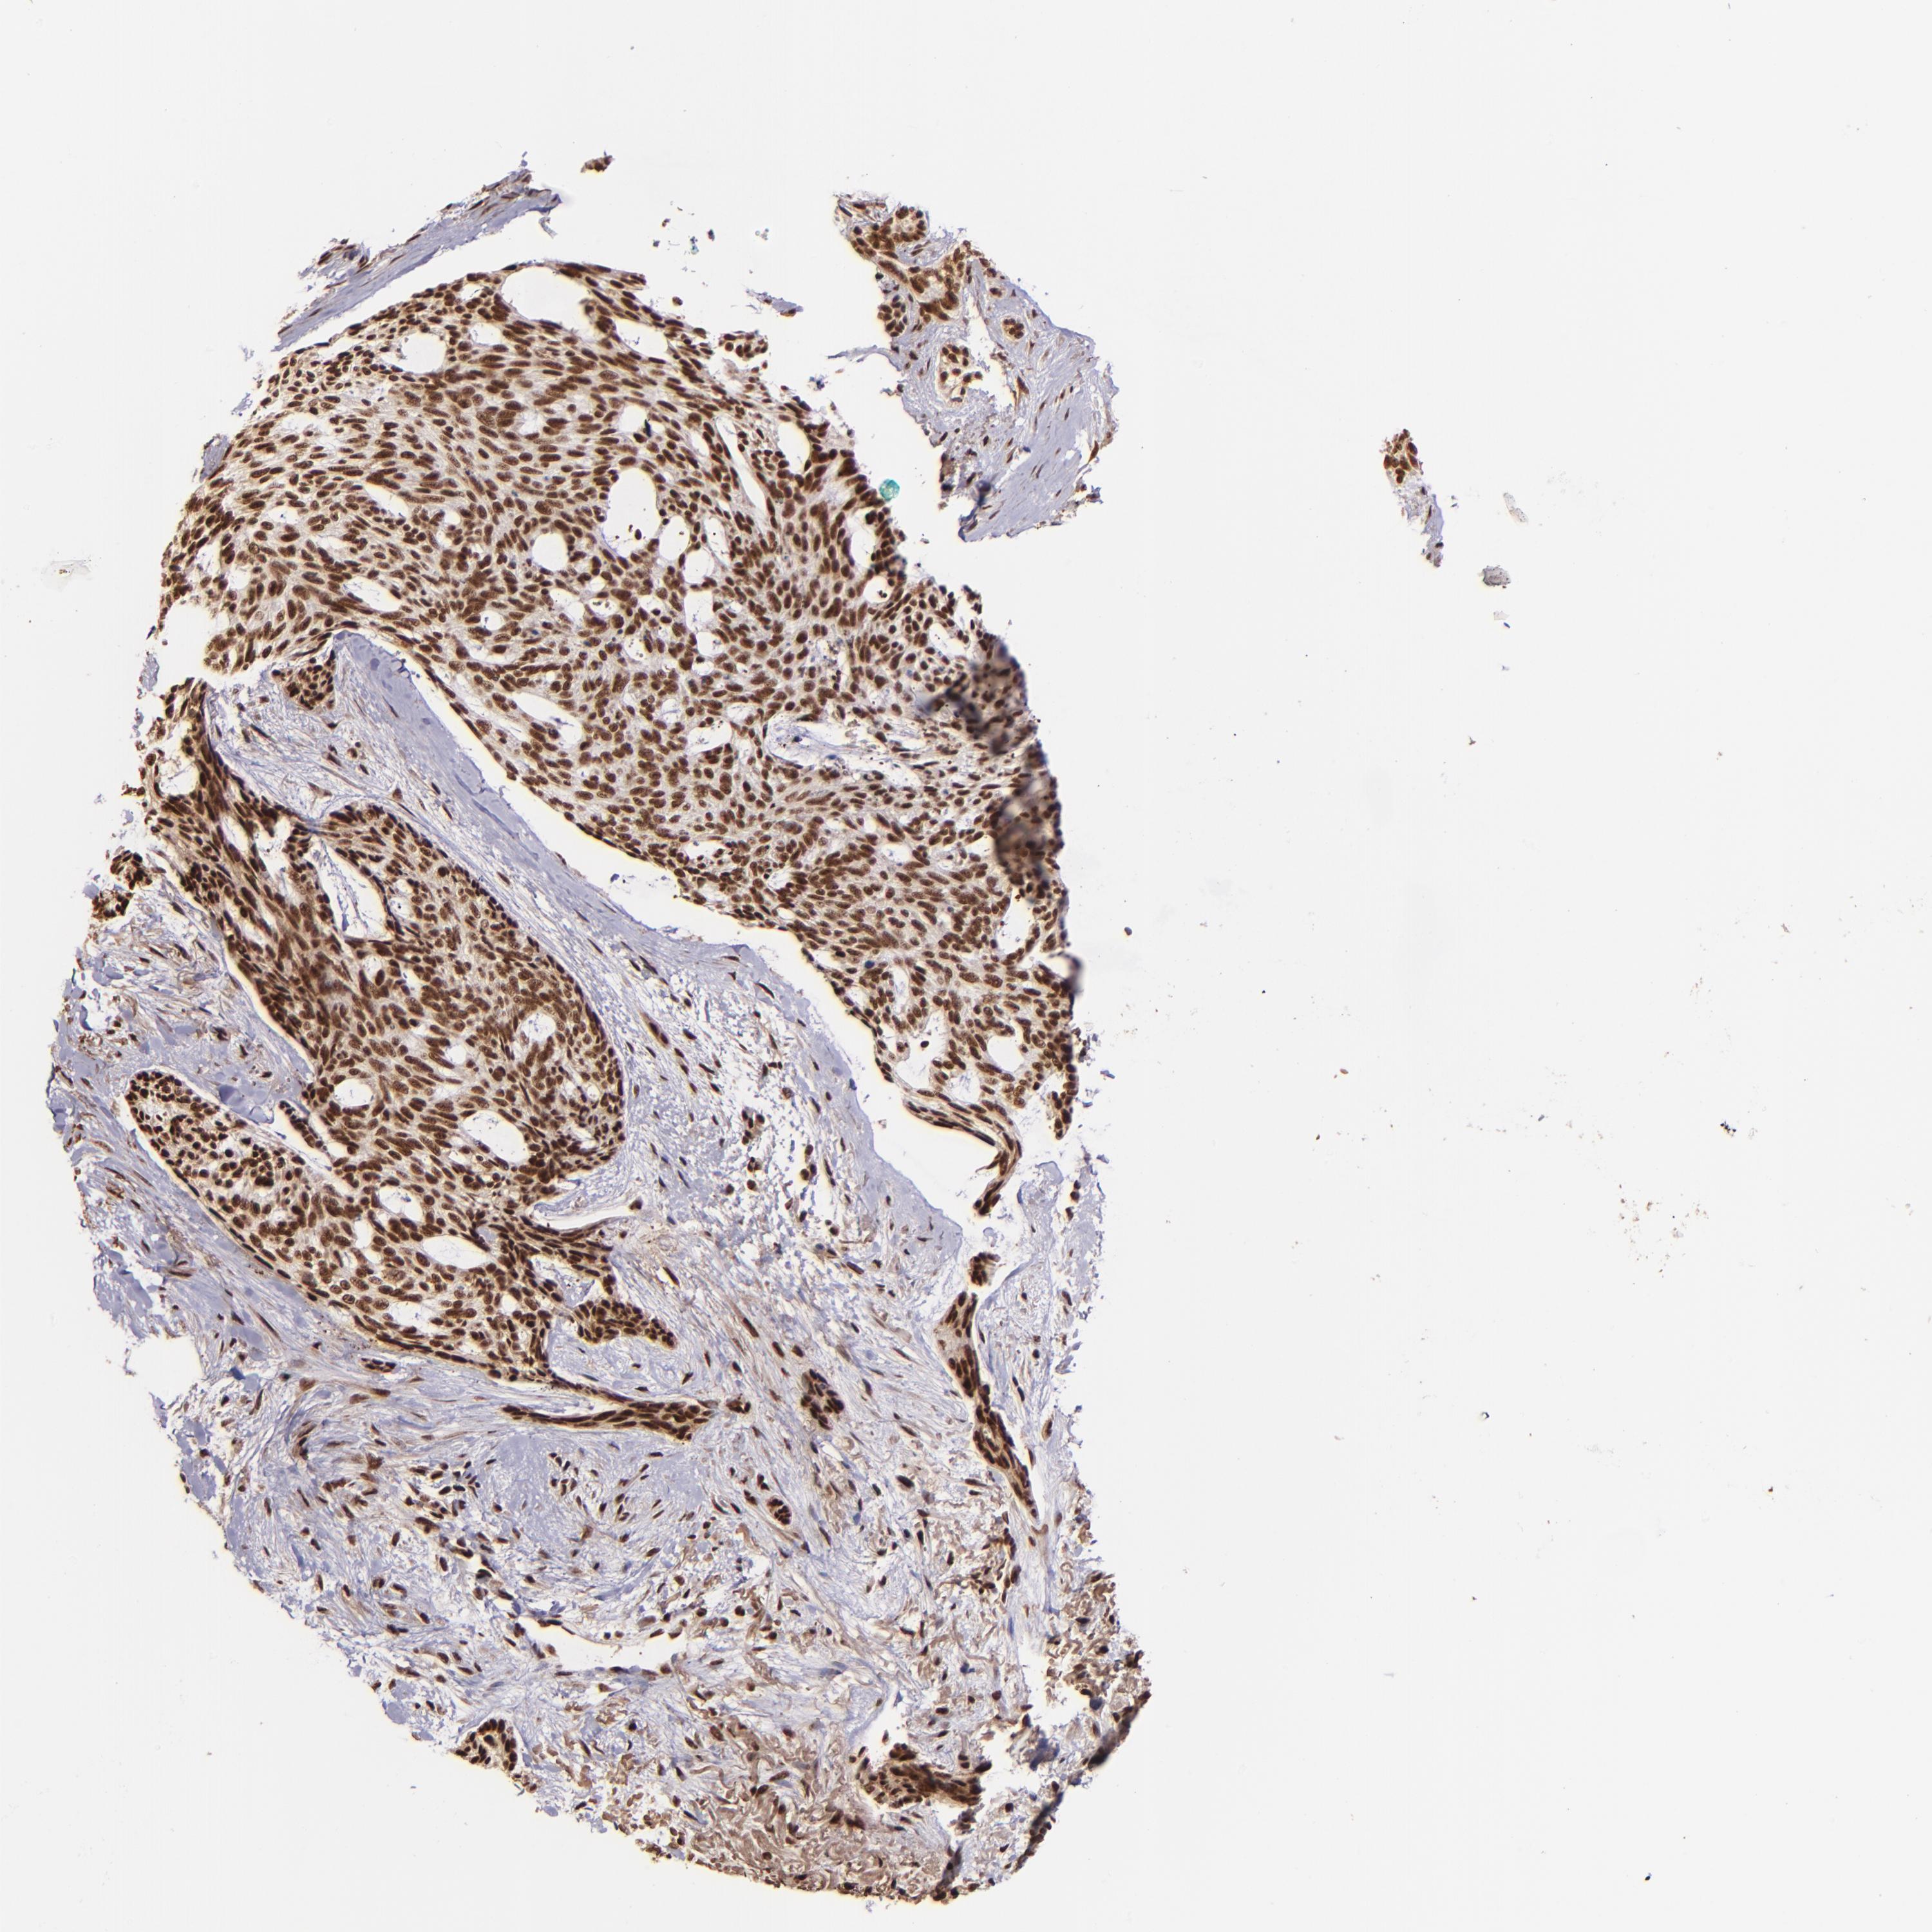

Basal cell and squamous cell cancer

SKIN CANCER - Protein expressioni

A mouse-over function shows sample information and annotation data. Click on an image to view it in a full screen mode. Samples can be filtered based on level of antibody staining by selecting one or several of the following categories: high, medium, low and not detected. The assay and annotation is described here.

Antibody stainingi

Antibody staining in the annotated cell types in the current human tissue is reported as not detected, low, medium, or high, based on conventional immunohistochemistry profiling in selected tissues. This score is based on the combination of the staining intensity and fraction of stained cells.

Each image is clickable and will lead to virtual microscopy that enables deeper exploration of all samples and also displays staining intensity scores, fraction scores and subcellular localization as well as patient and tissue information for each sample.

Antibody HPA001880

Staining

High

Intensity

Strong

Quantity

>75%

Location

Nuclear

Squamous cell carcinoma, NOS

Basal cell carcinoma